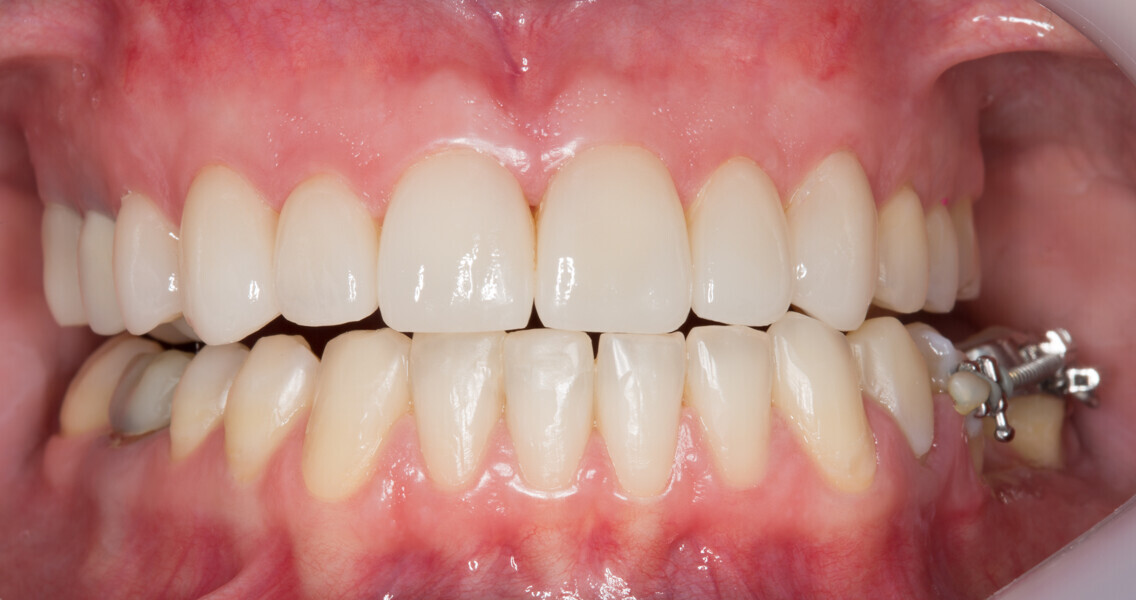

Fig. 25: Final results of the analogue and digital approach.

Fig. 26: Final results of the analogue and digital approach.

Fig. 27: Final results of the analogue and digital approach.

Fig. 28: Final results of the analogue and digital approach.

Fig. 29: Final results of the analogue and digital approach.

Fig. 30: Final results of the analogue and digital approach.

Fig. 31: Final results of the analogue and digital approach.